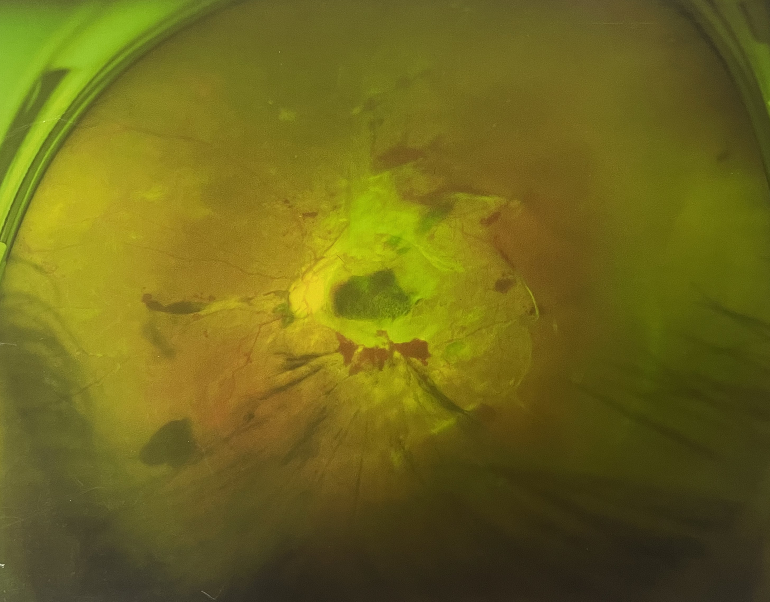

由于王女士的左眼沒(méi)有聽從醫(yī)生盡快做手術(shù)的建議,一直耽誤,從4月前的0.4視力逐漸下降到僅剩眼前手動(dòng),導(dǎo)致左眼發(fā)展到糖尿病視網(wǎng)膜病變VI期(屬于6期糖網(wǎng)中的晚期),已經(jīng)產(chǎn)生大量新生血管+纖維增值+廣泛牽拉性視網(wǎng)膜脫離,由于耽誤了病情,且病情發(fā)展異常迅速,導(dǎo)致目前左眼連保住眼球都很困難。

“而如果4月余前,左眼及時(shí)手術(shù)(當(dāng)時(shí)左眼病情比右眼輕,增殖膜還未累及黃斑),左眼將恢復(fù)的比右眼還好,甚至可以恢復(fù)到0.8或1.0,而現(xiàn)在連保住眼球的機(jī)會(huì)都很渺茫”,張小虎醫(yī)生表示實(shí)在可惜。

4個(gè)月前的左眼

左眼發(fā)展到糖尿病視網(wǎng)膜病變VI期